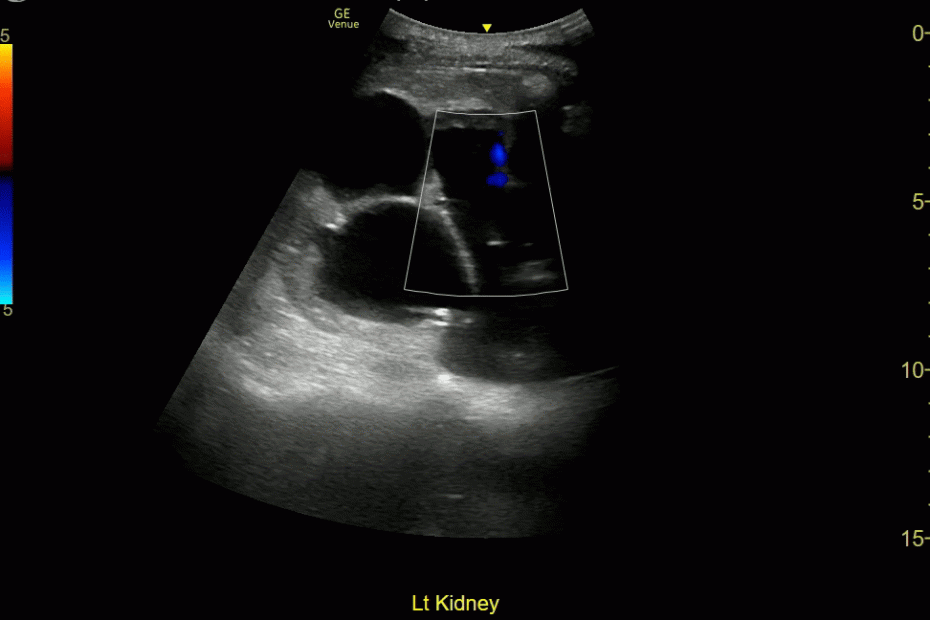

Prox Ureteral Stone, Sponge Kidney